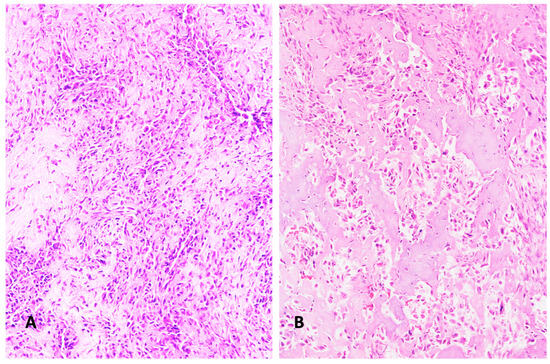

Better distinction between individual tumor types (osteoblastoma versus osteosarcoma; fibrous dysplasia versus low-grade central osteosarcoma) became possible, which had a direct impact on therapy decisions and modalities or evolved new therapeutic options (denosumab therapy in giant cell tumors of bone). Malignant tumors, which were previously considered as one group, albeit being a highly heterogeneous group, e.g., undifferentiated small round cell sarcomas of bone and soft tissue, could now be subdivided molecularly and genetically as distinct entities, and initial studies indicate that the therapy for each might also differ. So-called “tumor-like lesions,” which were previously considered reactive, also exhibited genetic aberrations that suggested their classification as true neoplasms (solitary bone cyst, non-ossifying bone fibroma).